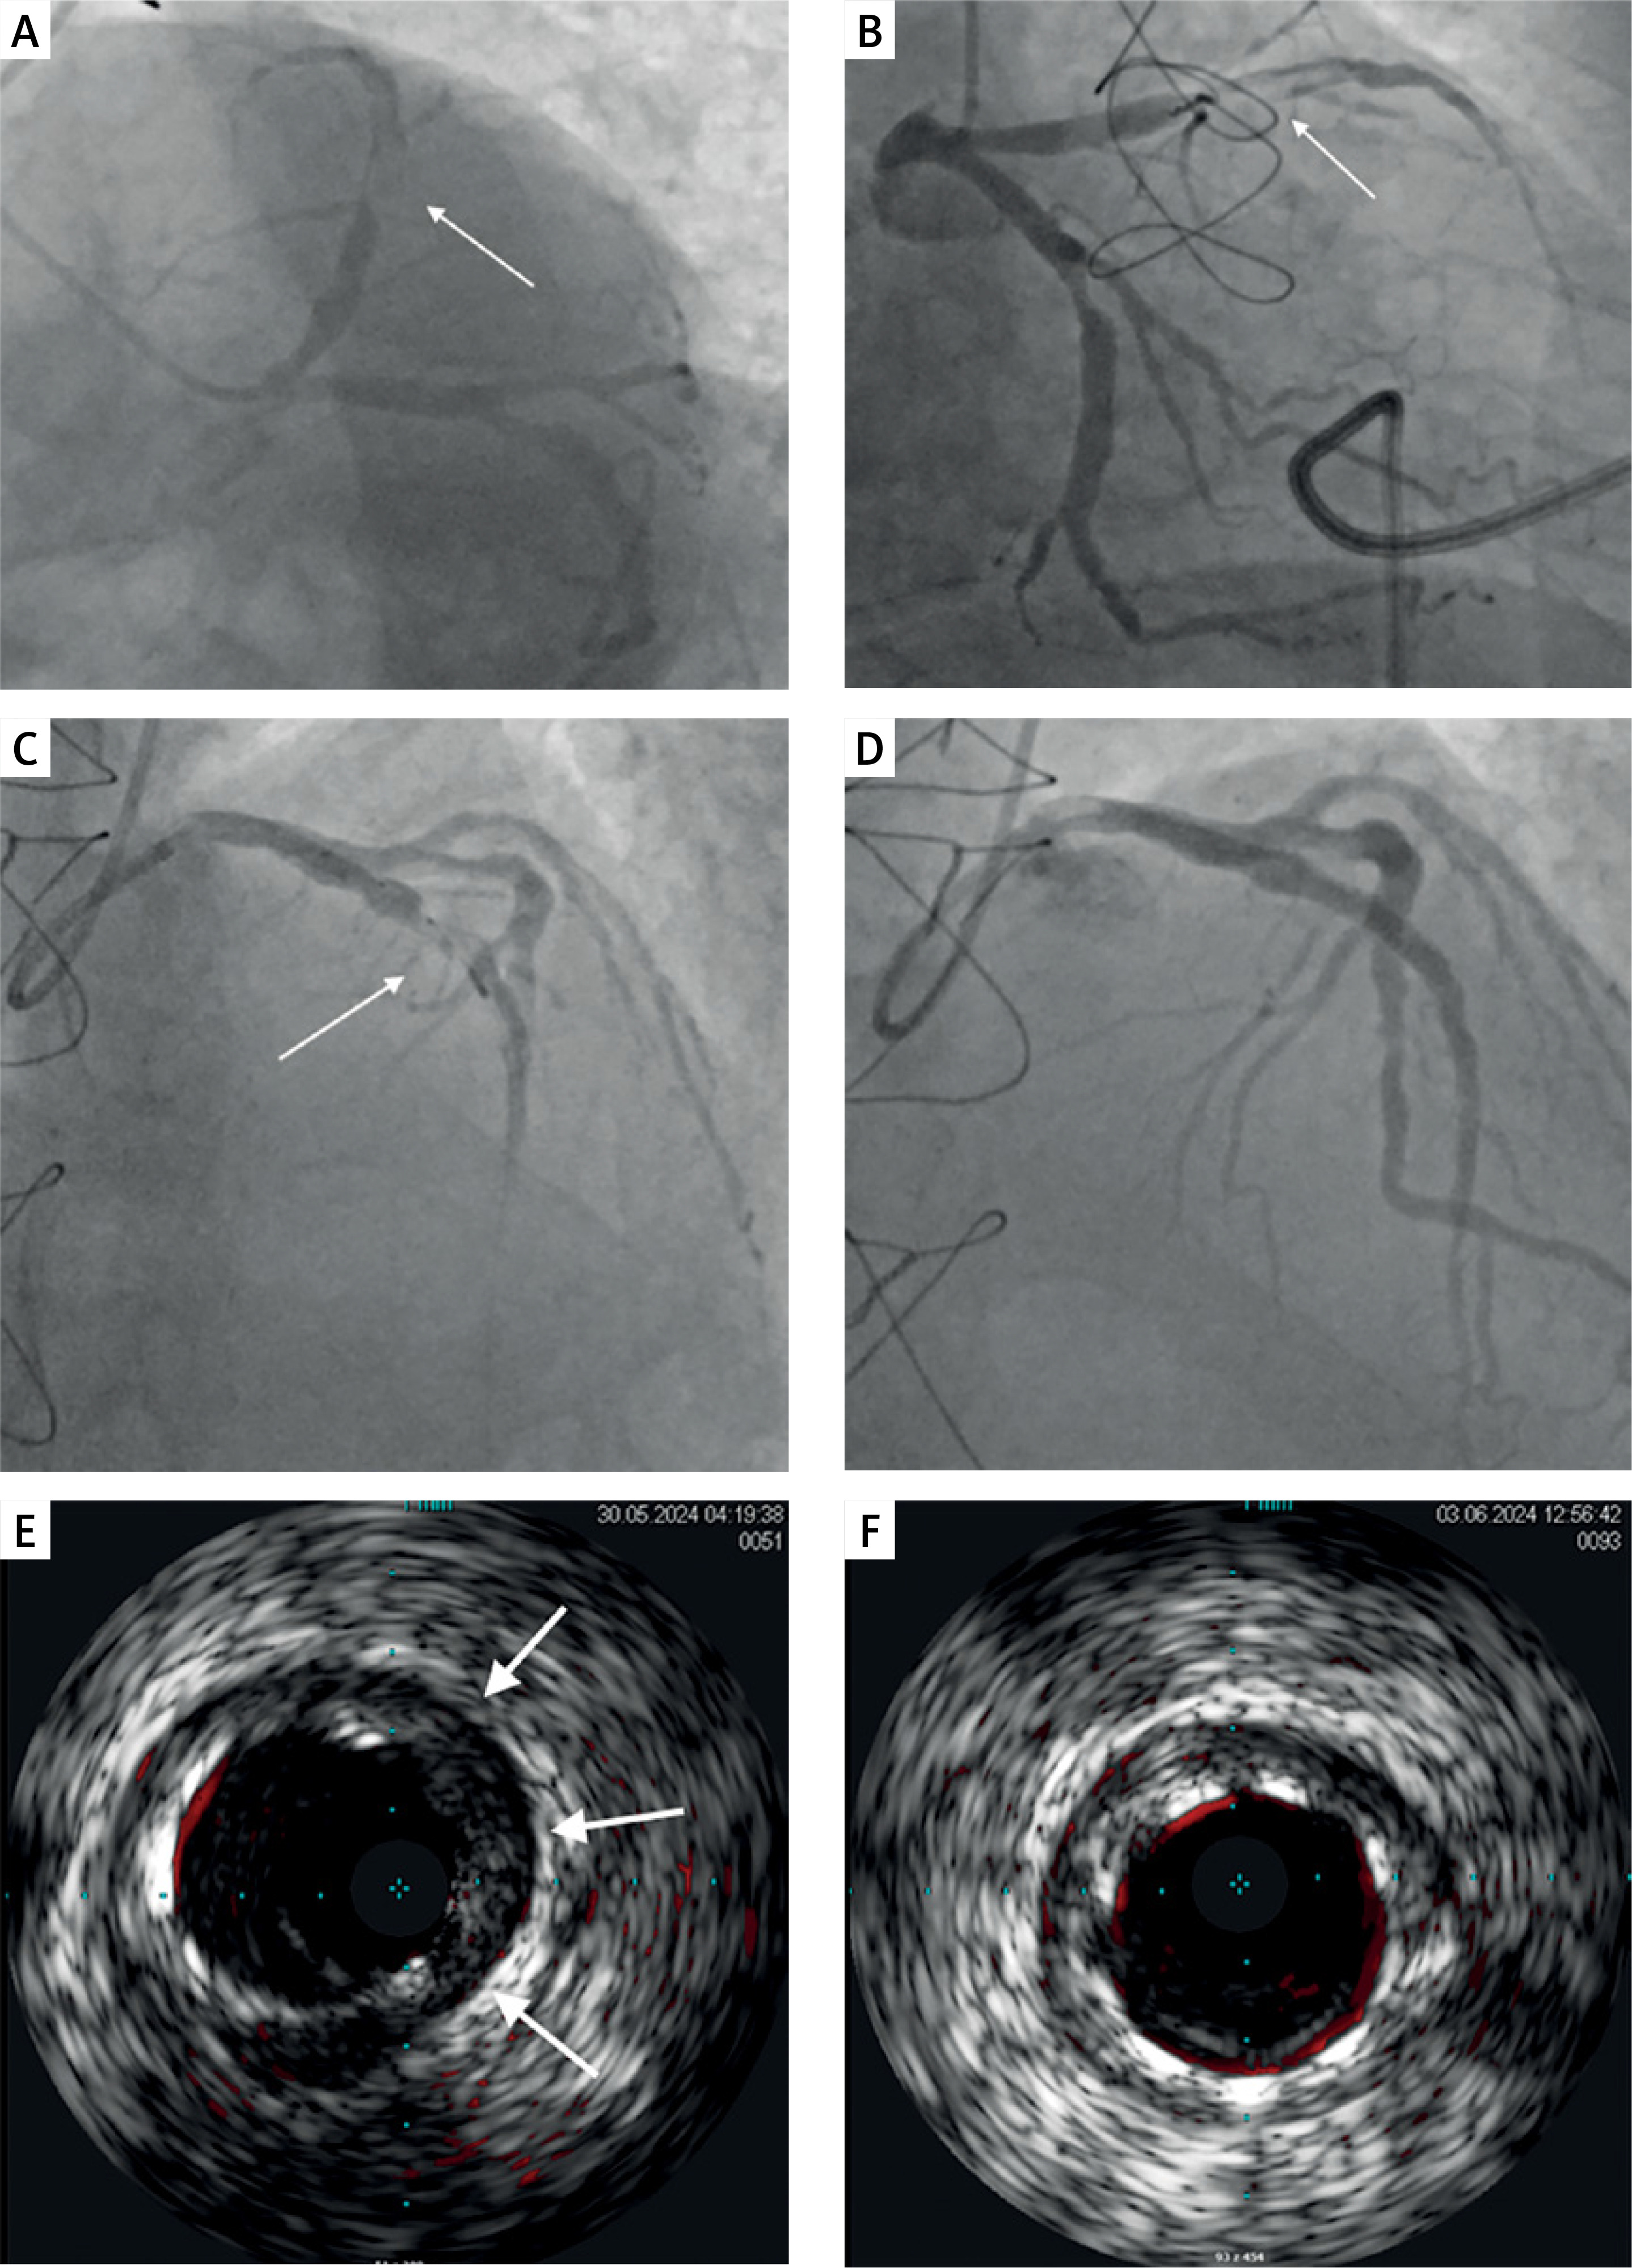

Figure 1

A – Initial coronary angiogram showing significant stenosis with high thrombus burden in the proximal left anterior descending artery (LAD) (arrow) and up to 60% stenosis in the circumflex artery. B – Initial coronary angiogram showing significant stenosis with high thrombus burden in the proximal LAD (arrow) and up to 60% stenosis in the circumflex artery. C – Thrombus aspiration using a 6F Export aspiration catheter (arrow). D – Coronary angiogram after drug-eluting stent implantation into the proximal LAD. E – Intravascular ultrasound (IVUS) imaging demonstrating stent underexpansion (arrows). F – Final IVUS imaging confirming optimal stent apposition after high-pressure post-dilatation

A 74-year-old man with arterial hypertension, hypercholesterolemia and a history of surgical treatment of pulmonary artery aneurysm presented with acute chest pain lasting over 15 h. His electrocardiogram showed T-wave inversion in leads V2-V4. Despite hemodynamic stability, he reported persistent chest pain. Transthoracic echocardiography revealed reduced left ventricular ejection fraction of 30% with akinesis of the apex and adjacent segments. Emergent coronary angiography via radial access revealed significant stenosis with extensive thrombus in the proximal left anterior descending coronary artery (LAD) with TIMI grade 2 flow (Figures 1 A, B). Additionally, the circumflex artery showed stenosis up to 60%. The patient was pretreated with unfractionated heparin, aspirin and prasugrel. A hybrid coating guidewire was advanced to the distal LAD using a 6F EBU guiding catheter. Thrombus aspiration was performed using a 6F Export catheter with four passes, successfully retrieving large thrombus fragments (Figure 1 C). For patient stabilization, an intracoronary bolus of abciximab (a glycoprotein IIb/IIIa inhibitor) was administered, followed by deployment of a 3.5 × 38 mm drug-eluting stent at 24 atm, achieving suboptimal sizing (Figure 1 D). Post-deployment imaging revealed slow-flow phenomenon. Intravascular ultrasound (IVUS) excluded dissection but confirmed stent malapposition (Figure I E). Given the impaired coronary flow and prolonged chest pain, stent post-dilatation was deferred. The patient received dual antiplatelet therapy and continuous abciximab infusion for 12 h, followed by therapeutic doses of low molecular weight heparin. Four days later, IVUS-guided percutaneous coronary intervention was performed for stent optimization. High-pressure inflations using non-compliant balloons (4.0 × 20 mm and 5.0 × 15 mm) at 16 atm achieved optimal stent sizing (Figure 1 F). No detriment in the flow was observed. The remaining hospitalization was uneventful. Guideline-recommended heart failure treatment was implemented. The patient was discharged in good condition after 7 days.